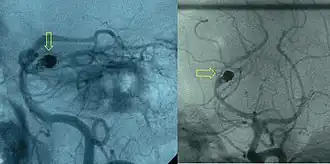

After a subarachnoid hemorrhage is confirmed, its origin needs to be determined. If the bleeding is likely to have originated from an aneurysm (as determined by the CT scan appearance), the choice is between cerebral angiography (injecting radiocontrast through a catheter to the brain arteries) and CT angiography (visualizing blood vessels with radiocontrast on a CT scan) to identify aneurysms. Catheter angiography also offers the possibility of coiling an aneurysm (see below).[4][30]

If a cerebral aneurysm is identified on angiography, two measures are available to reduce the risk of further bleeding from the same aneurysm: clipping[56] and coiling.[57] Clipping requires a craniotomy (opening of the skull) to locate the aneurysm, followed by the placement of clips around the neck of the aneurysm. Coiling is performed through the large blood vessels (endovascularly): a catheter is inserted into the femoral artery in the groin and advanced through the aorta to the arteries (both carotid arteries and both vertebral arteries) that supply the brain. When the aneurysm has been located, platinum coils are deployed that cause a blood clot to form in the aneurysm, obliterating it. The decision as to which treatment is undertaken is typically made by a multidisciplinary team consisting of a neurosurgeon, neuroradiologist, and often other health professionals.[4]

In general, the decision between clipping and coiling is made on the basis of the location of the aneurysm, its size and the condition of the person. Aneurysms of the middle cerebral artery and its related vessels are hard to reach with angiography and tend to be amenable to clipping. Those of the basilar artery and posterior cerebral artery are hard to reach surgically and are more accessible for endovascular management.[58] These approaches are based on general experience, and the only randomized controlled trial directly comparing the different modalities was performed in relatively well people with small (less than 10 mm) aneurysms of the anterior cerebral artery and anterior communicating artery (together the "anterior circulation"), who constitute about 20 percent of all people with aneurysmal SAH.[58][59] This trial, the International Subarachnoid Aneurysm Trial (ISAT), showed that in this group the likelihood of death or being dependent on others for activities of daily living was reduced (7.4 percent absolute risk reduction, 23.5 percent relative risk reduction) if endovascular coiling was used as opposed to surgery.[58] The main drawback of coiling is the possibility that the aneurysm will recur; this risk is extremely small in the surgical approach. In ISAT, 8.3 percent needed further treatment in the longer term. Hence, people who have undergone coiling are typically followed up for many years afterwards with angiography or other measures to ensure recurrence of aneurysms is identified early.[60] Other trials have also found a higher rate of recurrence necessitating further treatments.[61][62]